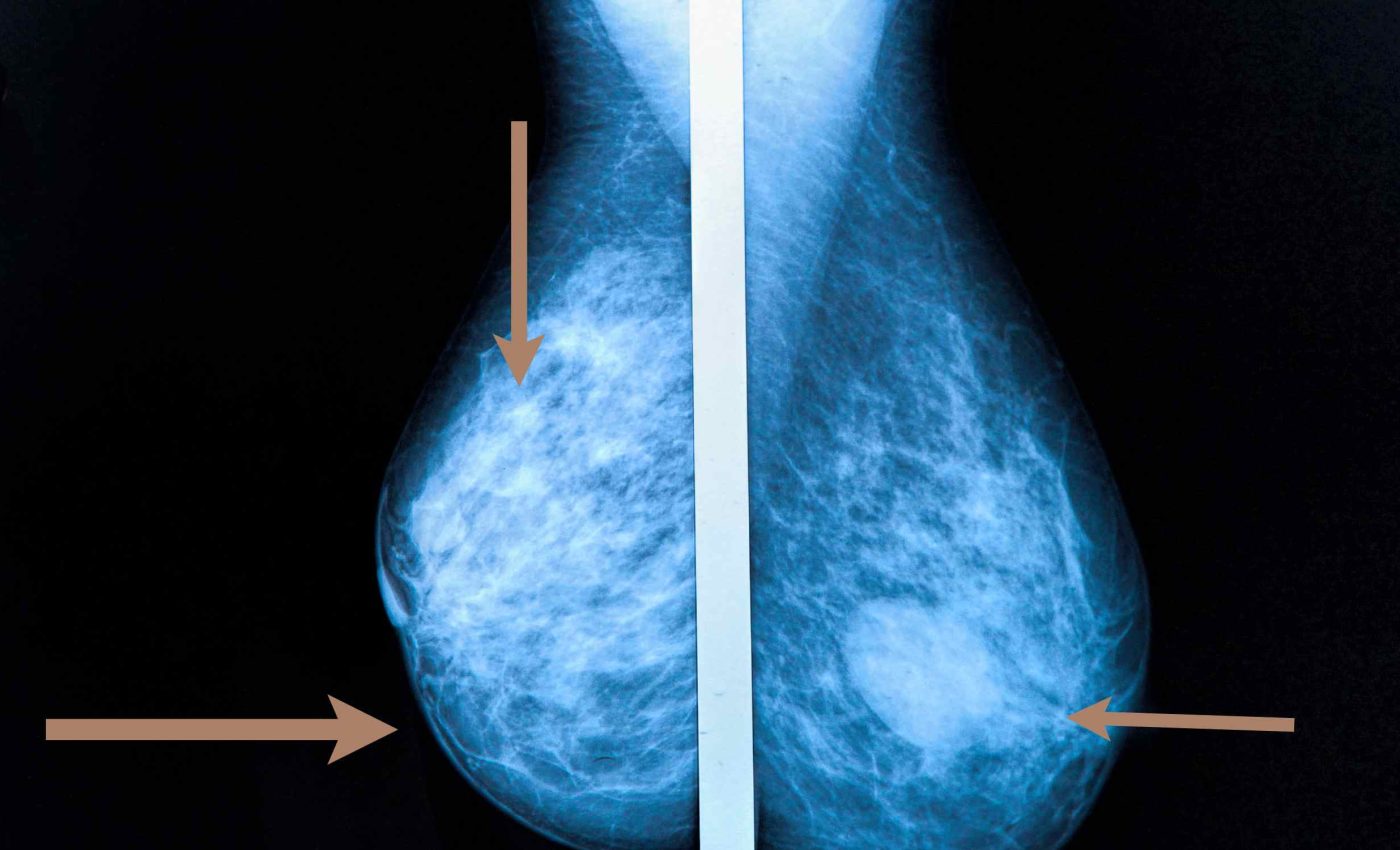

Healthcare providers encourage yearly visits that include mammograms, pelvic exams, and general tests that match a patient’s risk factors.

Different guidelines call for mammograms every 2 years for women who are between the ages of 50 and 74, and who are at average risk of developing breast cancer, based on recommendations from the U.S. Preventive Services Task Force.

One study by the Centers for Disease Control and Prevention (CDC) showed that 1 in 4 women aged 50 to 74 had skipped mammograms in the past 2 years.

Some statistics show that breast cancer causes more than 40,000 deaths in women each year in the United States.

Experts note that screening mammograms lower the chance of dying from breast cancer by about 22%.